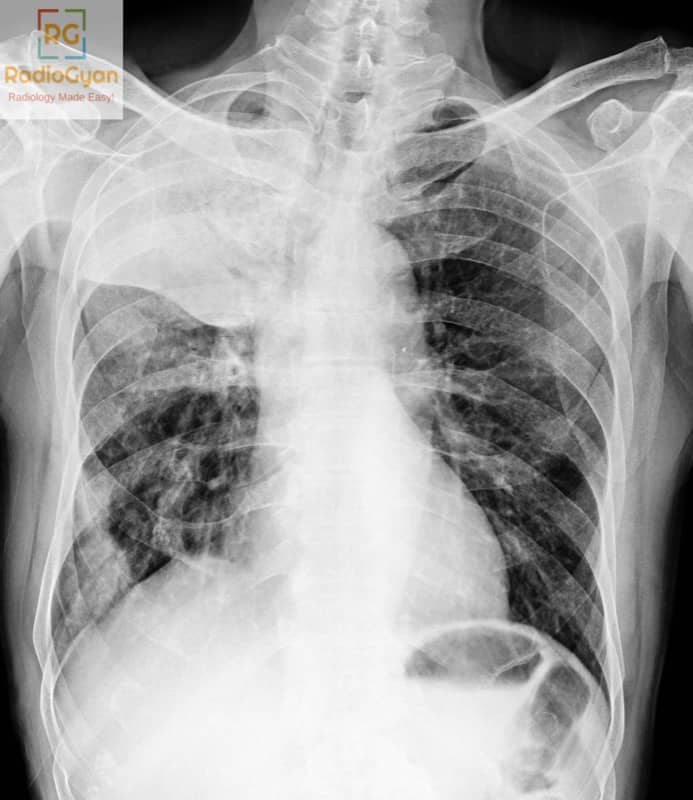

Golden’s S sign is caused by a central obstructing lesion, typically a bronchogenic carcinoma, located at the right hilum on an chest radiograph. This mass causes right upper lobe collapse (atelectasis) due to bronchial obstruction. Other causes can include metastatic cancer, enlarged lymph nodes, or any central lesion leading to right upper lobe collapse.

The sign is named after Dr. Ross Golden, who first described the sign in 1925. It is called Golden’s S sign because the contour of the right minor (horizontal) fissure and the adjacent hilar mass together form an S-shaped or reversed S-shaped shadow on a frontal chest X-ray.

A central mass at the right hilum obstructs the right upper lobe bronchus, causing partial or complete collapse of the right upper lobe. The elevated minor fissure assumes a concave shape laterally and a convex shape medially around the mass, producing the characteristic S-shaped or reversed S-shaped curve. This distortion reflects the opposing forces of lobar atelectasis pulling the fissure upward and the mass expanding the hilum, creating the distinctive radiographic appearance.